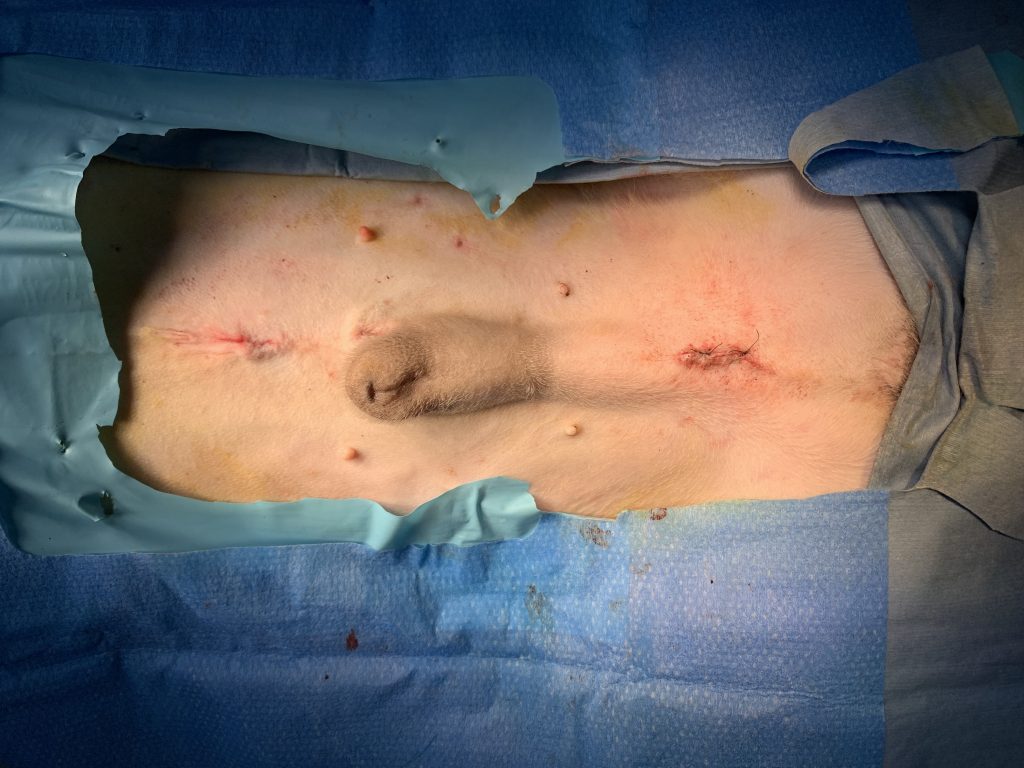

隱睪拿出後,我們利用鏡頭確認腹腔內沒有地方出血,接著就輕柔拔出trocar,關閉傷口。

微創的傷口,和傳統開腹差距是非常巨大的。

術後的傷口,是在腹正中線上兩個1公分左右的洞,以皮內縫合所以不用拆線。貓咪在手術後2個小時便順利回家。